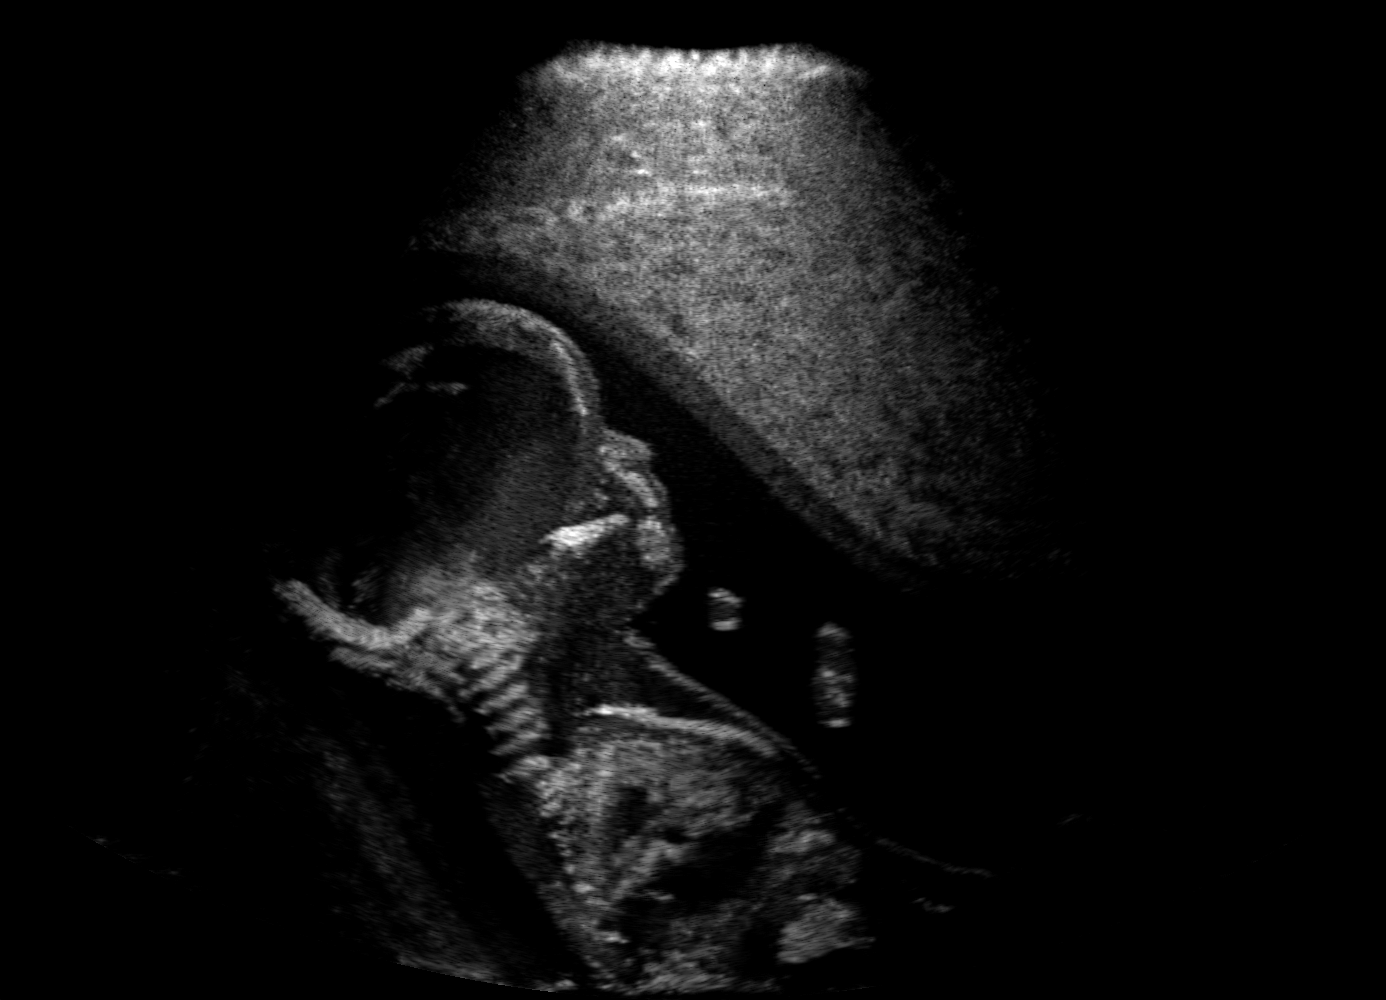

Qualitative evaluation.

Fig. 2 depicts the qualitative results for all the models mentioned above, with arrows pointing at structures relevant to discussion points below. The visual results of the ablated variants of SA2H show substantial quality degradation compared to the full SA2H model, demonstrating the importance of each proposed architectural contribution. Given only segmentation map in the network input, SA2H-att fails to generate acoustic shadows, e.g. those cast by the ribs. Detailed structures such as the cervical vertebrae are blurred out in the SA2H-concat results, which also contain hallucinated structures mainly due to insufficient preservation of input information along the encoding-decoding path. With SA2H-conv, checkerboard artefacts are observed due to the lack of proposed additional stride-1 convolutional layers. SA2H-noise without any explicit noise input is seen to be sub-optimal at generating textural details. The baseline method NSA2H fails to preserve anatomical structures and acoustic shadows in all cases, while the simulated textures also show significant artefacts such as checkerboard patterns. Realism of different simulation aspects may become relevant given different clinical applications and scenarios. For instance, improved structural preservation, e.g. with the hyperechoic bony structures such as the skull and the ribs, of the final model over its ablated variants and NSA2H may prove relevant in fetal head measurements, while the textural improvements facilitating screening fetal organ maturity, e.g. lungs. Compared to the silver-standard model LSA2H with a low-quality rendered image as additional input, SA2H is seen to be on par in structural preservation. Note that shadowing on homogenous regions (e.g. the rib shadowing on the homogenous lung region on the 4th column of Fig. 2) with our proposed method SA2H is represented more faithfully compared to LSA2H, whereas shadows on structurally complex regions (e.g. the skull shadowing around the heart and surrounding tissues on the 3rd column of Fig. 2) are suboptimal with our SA2H. Therefore, one may have to evaluate our method given particular simulation tasks, e.g. its clinical validity for fetal heart exams. However, even with low quality rendered images, LSA2H leads to artificial enhancements of intensities, lack of acoustic shadows, and low-quality textures especially near the probe, for which SA2H yields satisfactory results as illustrated in Fig. 2.